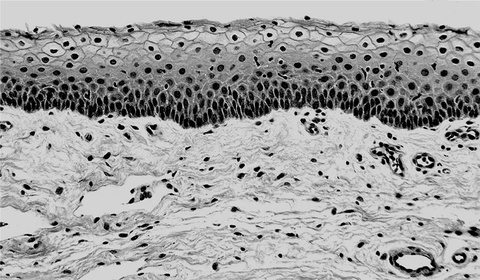

Illustration of cellular barrier

The human vaginal mucosa (thick, dark layer of cells at the top of the picture) is a cellular barrier that physically prevents pathogens and dirt from entering the body. Bacterial toxins called superantigens interact with CD40 molecules on the mucosa surface and trigger chemokine production. This leads to disruption of the barrier and allows the superantigens and in many cases the bacteria themselves to penetrate and causes serious and often fatal diseases, including toxic shock syndrome.